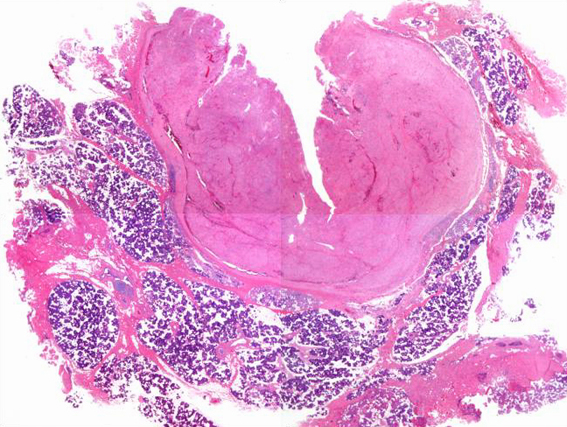

| 腫瘍のルーペ像.唾液腺内の線維性被膜を有した境界明瞭な充実性腫瘍. |